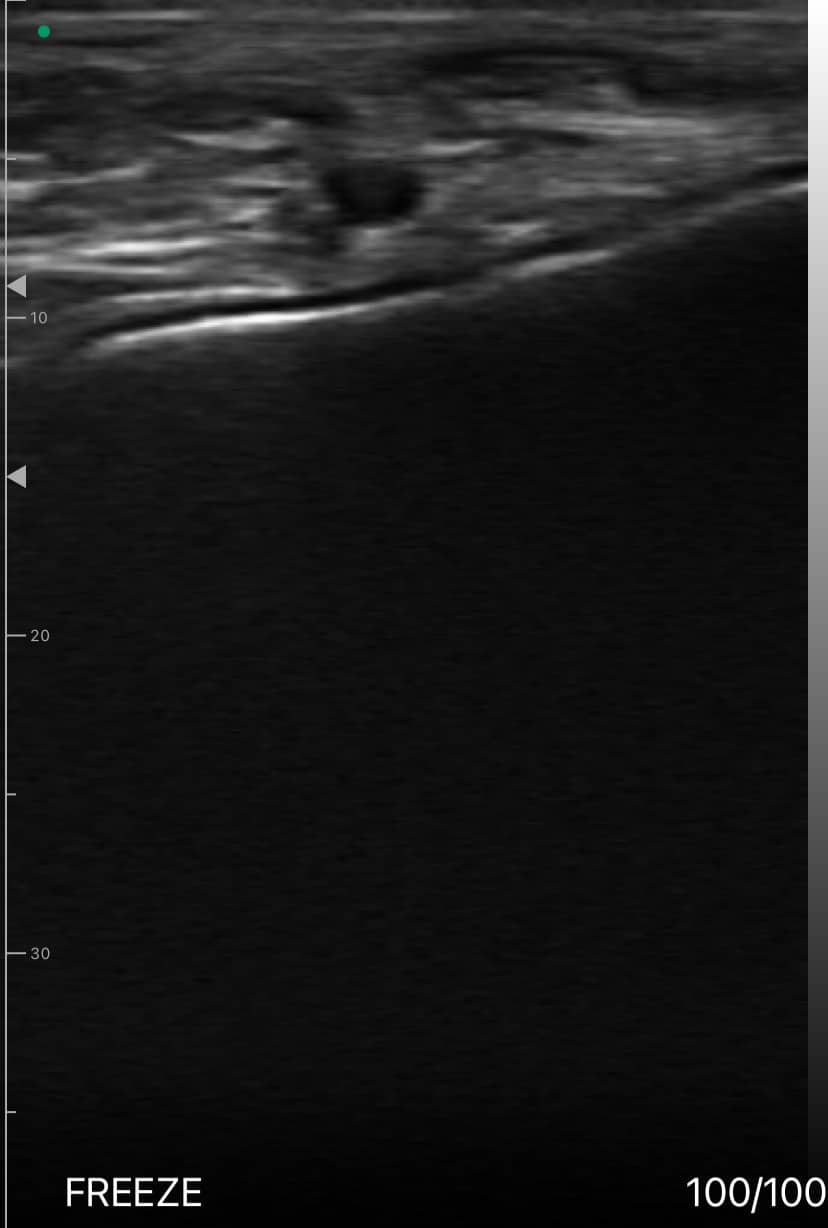

Échographie longitudinale du tendon d'Achille

Pied